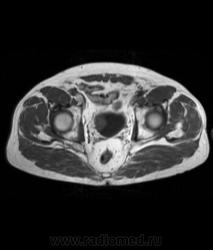

Для динамического контрастирования требуется инъектор, у нас с ним технические неполадки, поэтому контрастное вещество вводим от руки. Но в данном случае четко видно проростание опухолевого компонента через мышечный слой мочевого пузыря, даже некоторой инфильтрацией паравезикальной клетчатки. По гистологии плоско-клеточный рак. У пациента множественные метастазы в легких.